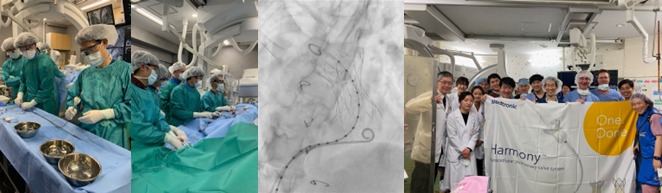

- これまで唯一の治療選択肢は開胸手術でしたが、無症候で患者年齢が若いため、適切な時期に手術が行われてきませんでした。そこで、低侵襲で短い入院期間で済む経カテーテル肺動脈弁留置術(TPVI)が開発されました。最新の肺動脈弁専用弁であるHarmony弁を用いたTPVIが日本で認可され、2023年3月2日に当院で国内初の治療が行われました。

図6:当院で行われた、国内初のHarmony TPVI治療(2023/3/2)